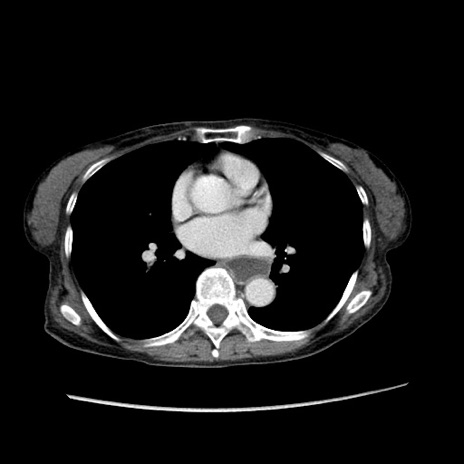

症例25(横断像)

【症例】80歳代女性

【主訴】胸のつかえ感

【現病歴】約9時間前に食後から胸のつかえた感じあり、嘔吐あり、来院。

【既往歴】胃癌(全摘)、胆摘、虫垂炎

【身体所見】心窩部に圧痛あり、反跳痛なし。

【データ】WBC 5700、CRP 0.05